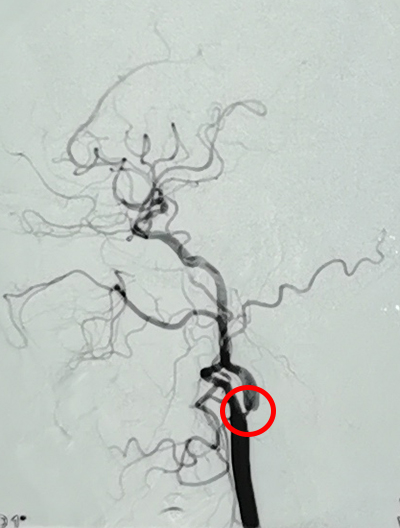

刘女士的造影

? 右侧颈内动脉重度狭窄(70~99%)

? 短暂性脑缺血发作